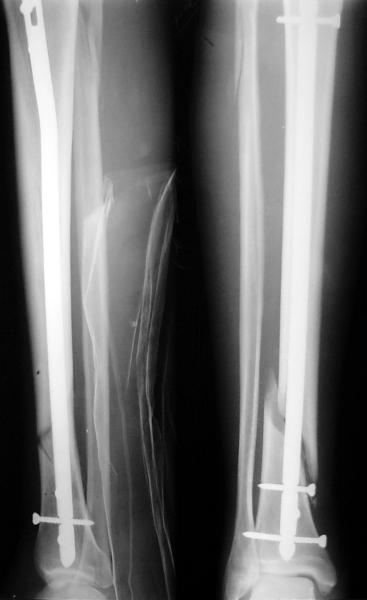

Как мне показать пример? Фото стоящего на одной оперированной конечности пациента? O! Пример, подвигнувший нас на некоторое изменение технологий. Пациент этот ходил с полной нагрузкой вопреки рекомендациям. В качестве подтверждения - сломанный проксимальный статический винт к 1 мес., а к 2 мес. - все остальные. Сейчас мы перешли на более fool-proof остесинтез.

На мой взгляд, на снимках, приведённых Вами - неправильно сростающийся перелом дистальной трети большеберцовой кости, состояние после остеосинтеза интрамедуллярным гвоздём.

Как Вы пишите снимок под номером 1 - менсяц после операции, под номером 2- два месяца после операции.

Вы не послали послеоперационный снимок, поэтому трудно судить о состоянии редукции после операции.

I think that the X-Rays show S/P IMN of Spiral # of the Distal Tibia consoles in misalignment.

You wrote that a picture number 1 - f month after the surgery, and number 2-two months after the surgery.

You have not sent a postoperative X-Rays; so it's impossible to discuss about the condition of a reduction after operation.